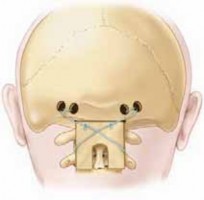

1. At the level below the transverse sinus, four transverse-oriented holes are drilled through both cortices of the occiput with a high-speed diamond drill.7

1. The holes are aligned transversely with two on each side of the midline. At least 1 cm of intact bone should be left between the holes to prevent wire pull-out through the skull (

TECH FIG 1A

).

2. Surgical loupes and a headlamp are recommended for this procedure.

2. Using a high-speed diamond burr, the surgeon makes a transverse-oriented trough into the base of the occiput to fit the rectangular superior part of the iliac autograft.

5. 16- or 18-gauge wire is passed through the burr holes on each side of the midline and the wire is looped on itself (

TECH FIG 1C,D

48. A sublaminar wire is placed under the ring of C2 or C3 (or passed through the base of the spinous process, if structurally sufficient, or if there is canal stenosis).

1. The left side of the graft accepts the left end of the wire and the right end of the graft accepts the right end of the wire (

TECH FIG 1E

49. The edges of the graft are contoured to fit appropriately into the occipital trough and around the base of the spinous process (

TECH FIG 1F

50. The wires are tightened over the graft in figure 8 shape. After satisfactory tightening the edges of the wire are cut and bent away from skin (

TECH FIG 1G,H

Transverse sinus TECH FIG 1 • A. Four transverse-oriented occipital burr holes and rectangular trough. B. Corticocancellous rectangular graft with a notch at the inferior base ofA B the graft. _(continued)_EH